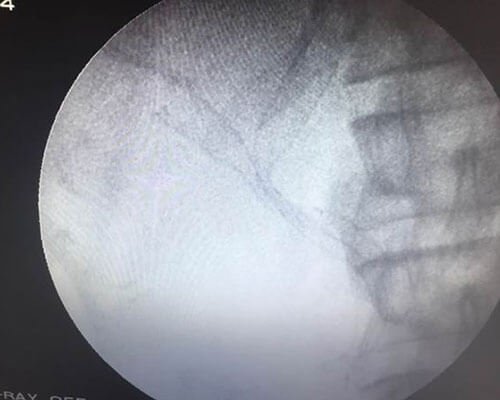

ERCP is performed by the oral route after sedation. During ERCP, bile duct and pancreatic ducts are evaluated after injection of contrast agent, and various therapeutic procedures can be performed

During ERCP stones can be removed form CBD or pancreatic duct and stents can be placed in CBD for treatment of jaundice and in MPD for pain relief